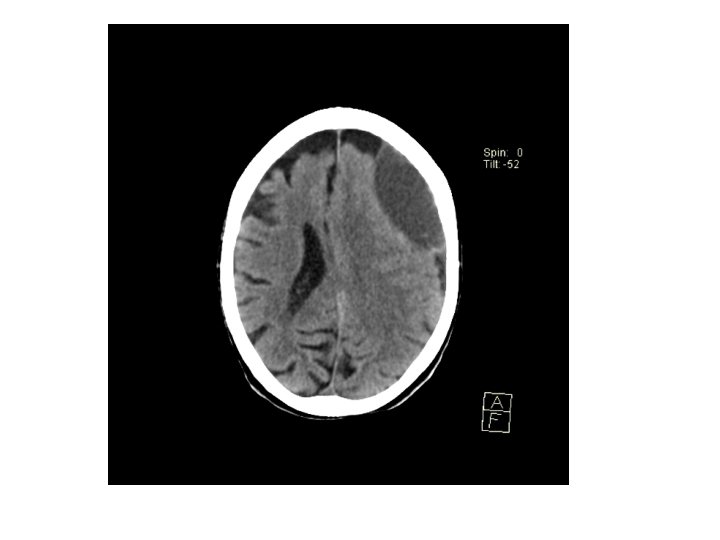

Chronic Subdural haematoma • • Hypodense lesion There might not be midline shift If asymptomatic, serial CT monitoring If symptomatic, burr hole craniostomy